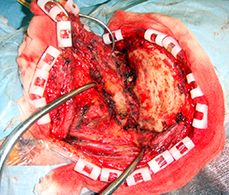

症例1) 65歳男性、頭蓋底部巨大髄膜腫、外科手術のみ

< 手術所見 >